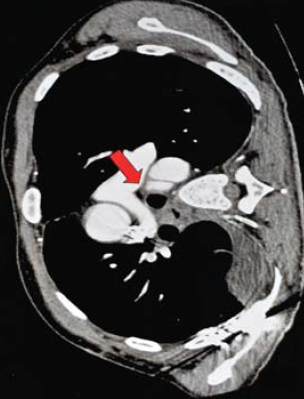

1. ábra.

Autóbalesetben sérült 26 éves ffi. DSA felvétele 3 héttel a baleset után. Az isthmicus szakaszon álaneurysma ábrázolódott.

1. 26 éves ffi autóbalesetben utasként szenvedett el mellkasi zúzódást, bordarepedést és tüdő contusiót. A kiszélesedett mediastinum és kis mennyiségű mellkasi folyadékgyülem vetette fel isthmicus tompa aortasérülés lehetőségét, amit DSA vizsgálattal igazoltunk. Hypotenziv kezelés mellett keringése stabil, a mediastinum kiszélesedése és haematologiai statusa nem változott. 3 héttel a sérülést követően bal oldali thoracotomia útján aorto-aorticus Dacron grafttal, mesterséges keringés alkalmazása nélkül, interpositiot végeztünk (1.,2.,3. ábra).